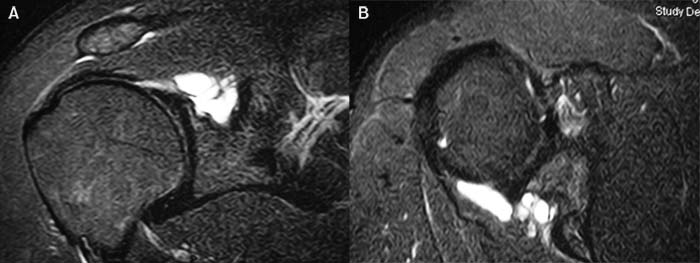

La indicación temprana de la cirugía se debe realizar en pacientes que presentan signos de compresión del nervio supraescapular secundario a ganglión en la fosa espinoglenoidea (Figura 4).47

Figura 4: Ganglión Espinoglenoideo con compresión del Nervio Supraescapular.